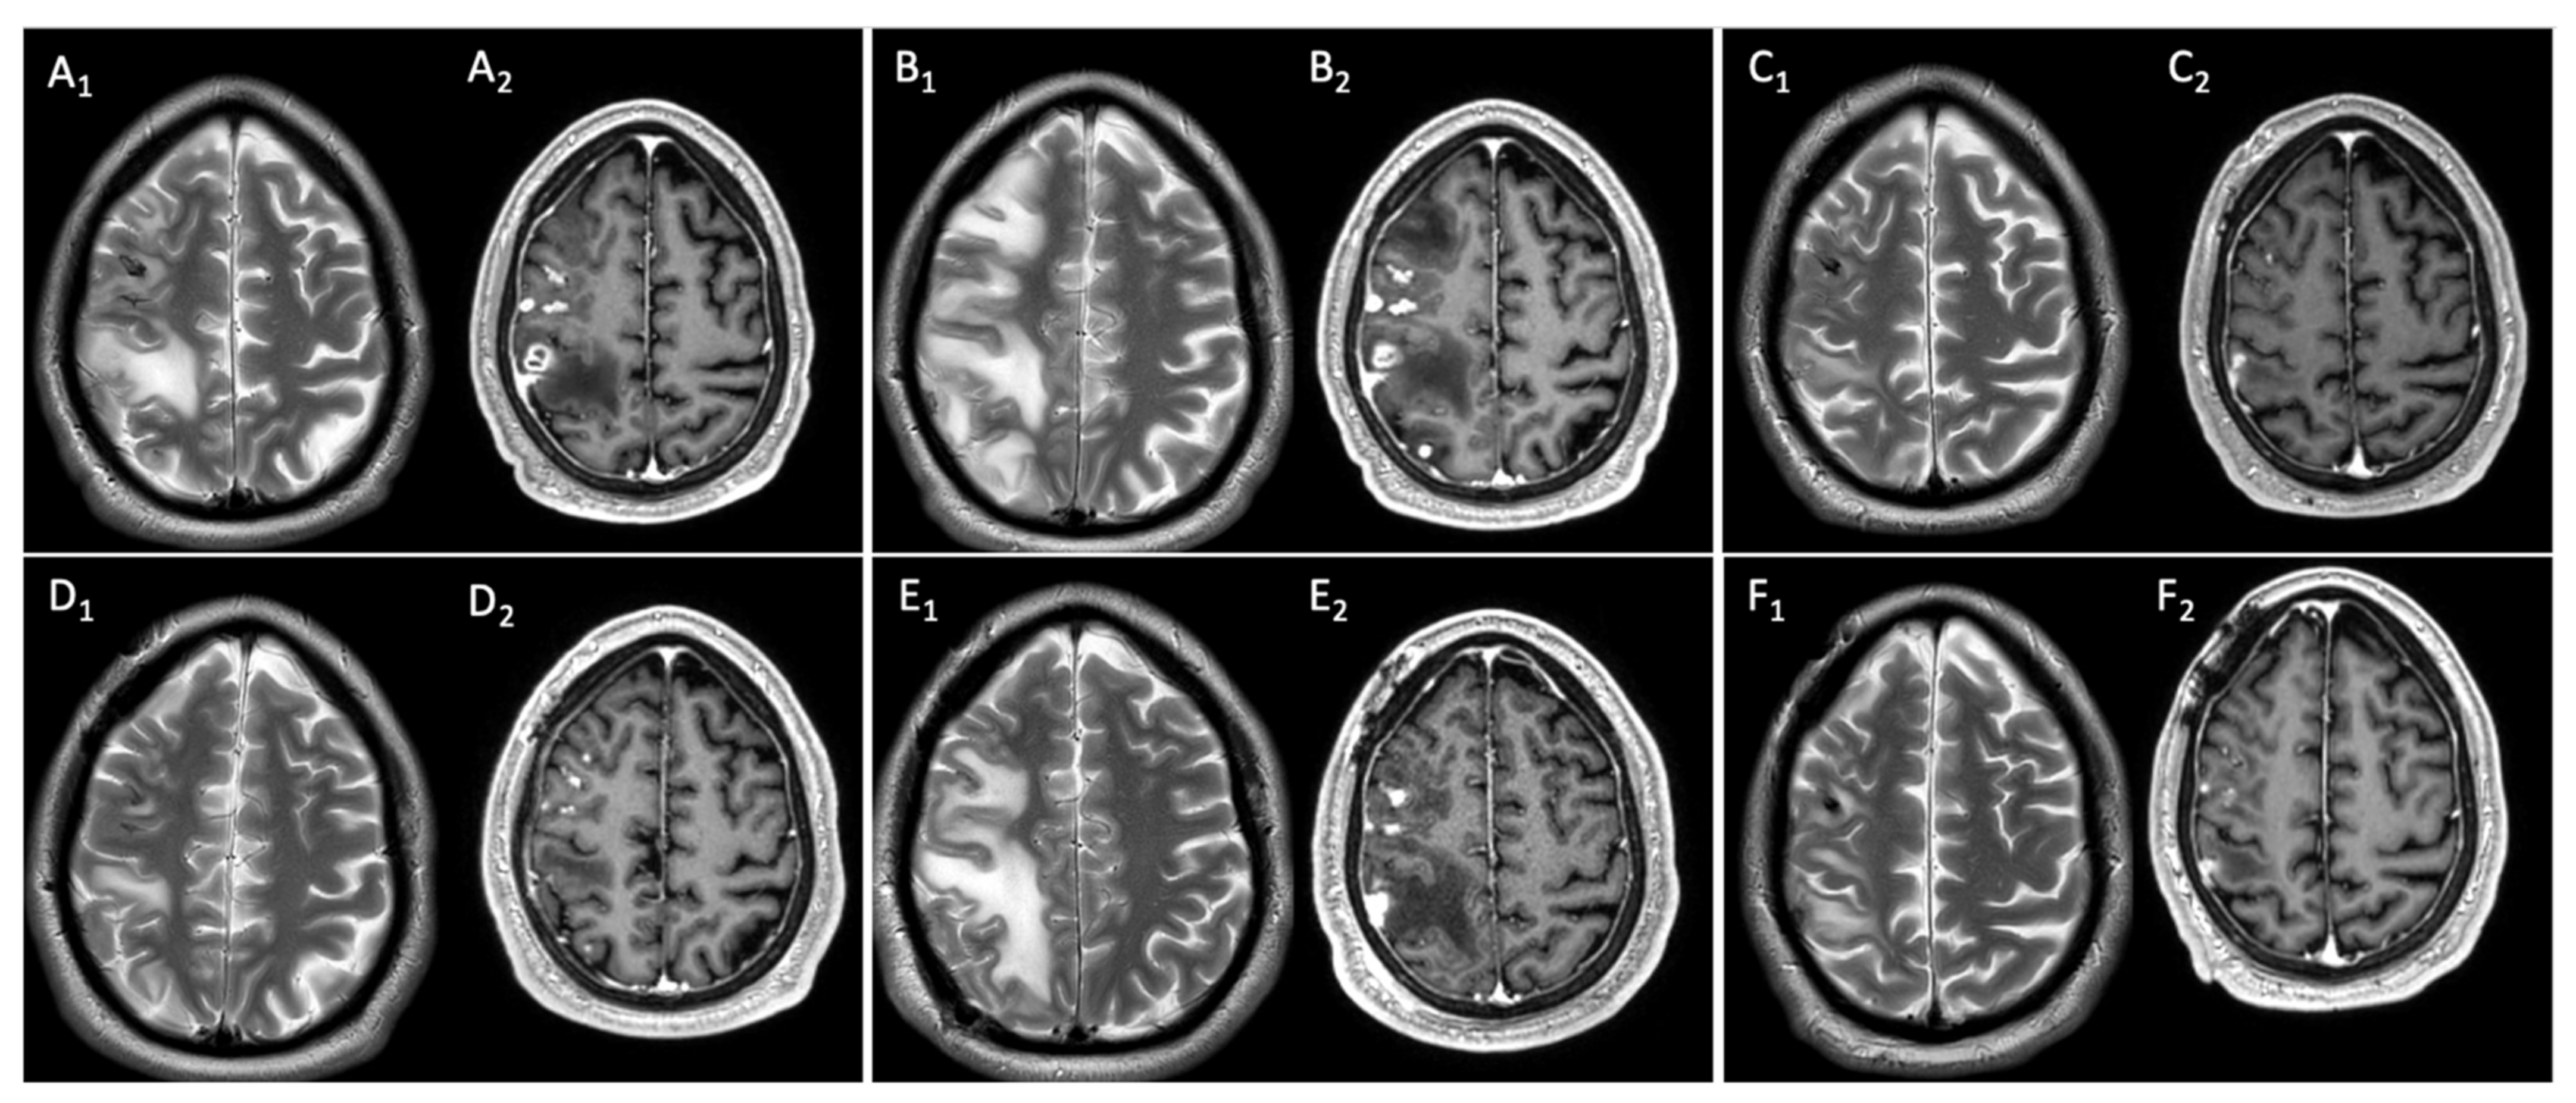

2.2. Clinical and Neuroimaging Follow-Up of Central Nervous System Infectious Lesions

2.2.1. Case Presentation

2.2.2. Case Discussion and Literature Review